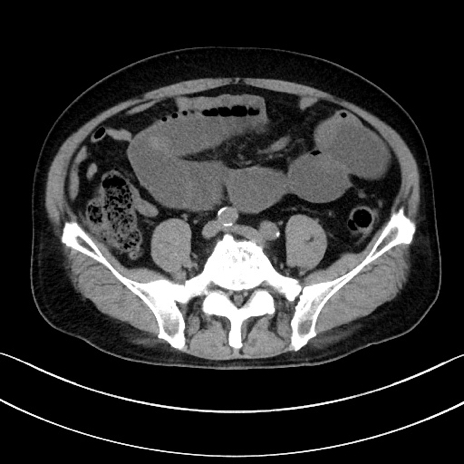

冠状断像

【症例】70歳代男性

【主訴】腹痛

【現病歴】今朝から腹痛あり。全体的に痛い。特に左上の方。排ガスが今日はない。冷や汗が出る。

【既往歴】直腸癌術後

【身体所見】左側腹部〜上腹部に圧痛あり。腹膜刺激症状明らかなではない。軽度反跳痛。左下腹部に術後瘢痕あり。

【データ】WBC 7700、CRP 0.02